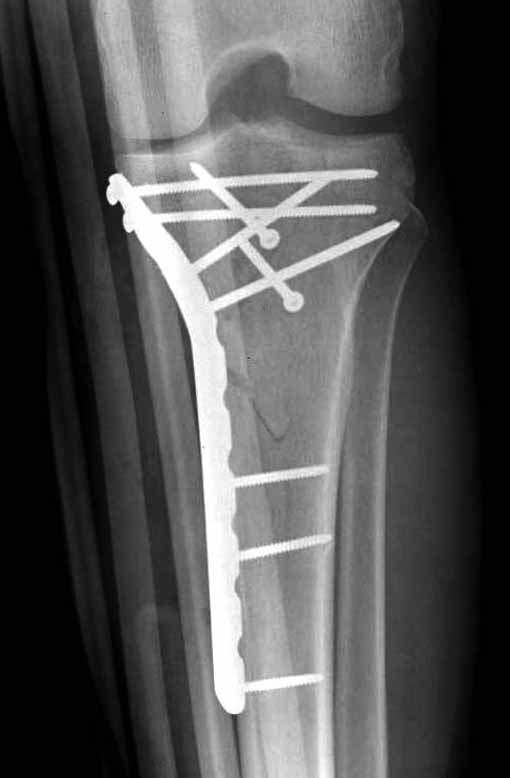

Двухколоннный перелом тибиал плато с вовлечением проксимального диафиза. Внутрисуставной компонент без смещения, и такой перелом можно лечить любым из описанных методов, о которых говорят наши коллеги.

Удобно аппаратом Илизарова или интрамедуллярным гвоздем. Гвозди не так сложно, как пугают, тем более Александр готов помощь с методичкой. Сперва надо установить компрессирующие шурупы на мыщелки. Давно отказались в пользу 3.5-4.0 мм кортикальных вместо толстых спонгиозных, потому что не доказаны преимущества толстых шурупов. Тонкие шурупы в субхондральной зоне смотрятся намного элегантнее, чем толстые 6.5.

Это мероприятие превращает перелом в простой диафизарный, который легко можно фиксировать гвоздем. Шурупы надо установить сзади предполагаемого места введения гвоздя.

В приложении этапы фиксации Both Column Fx и пластиной Synthes для плеча при переломе медиального мыщелка.